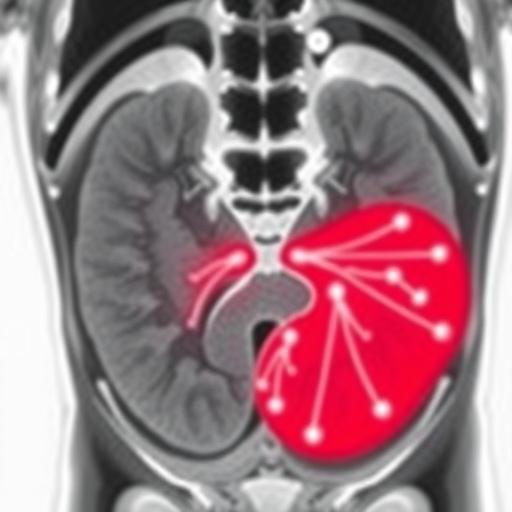

Prostate cancer recurrence poses a formidable challenge in oncological care, often eluding detection by standard imaging modalities such as bone scans and computed tomography (CT). The innovative PSMA PET scan involves the intravenous administration of a radiolabeled molecule engineered to selectively bind PSMA, a cell surface protein abundantly expressed on prostate cancer cells. This molecular targeting ensures high-contrast images by highlighting metastatic deposits with exceptional specificity and sensitivity. The study conclusively demonstrates that PSMA PET scanning identifies sites of cancer recurrence with a detection rate of approximately 70 percent, substantially surpassing historical detection rates ranging between 10 and 20 percent achieved by traditional imaging.

Technically, PSMA PET imaging leverages positron emission tomography’s capability to detect gamma rays emitted indirectly by the radiotracer administered to patients. The tracer binds to PSMA-expressing prostate cancer cells with high affinity, accumulating in both primary and metastatic tumor sites. This accumulation generates high-resolution three-dimensional images, allowing physicians to visualize cancer spread with unparalleled clarity. Such precision imaging reduces uncertainties inherent in conventional scans and significantly improves staging accuracy.